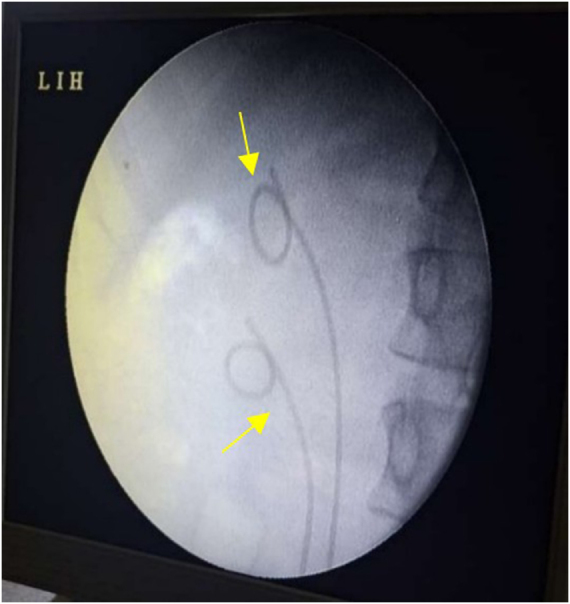

Case presentation: A 23-year-old female presented in a tertiary care hospital with intermittent right flank pain and recurrent UTIs for 3 months. Imaging revealed a right-sided duplex system with an intravesical ureterocele and functioning upper moiety. TFL deroofing was performed, with placement of dual DJ stents. Operative time was 40 minutes with negligible bleeding. Recovery was uneventful, and stents were removed at 6 weeks. At 6 months, imaging confirmed resolved hydronephrosis and preserved function; the patient remained asymptomatic at 12-month tele-follow-up.